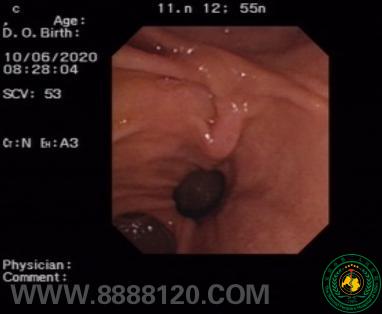

ERCP取石手术过程

①十二指肠镜探查肠腔,见十二指肠乳头旁憩室,增加插管难度②置入斑马导丝,多次插管均进入胰管,遂保留导丝

③采用导丝占据胰管法,行十二指肠乳头肌预切,第二导丝成功插入胆管④成功取出结石